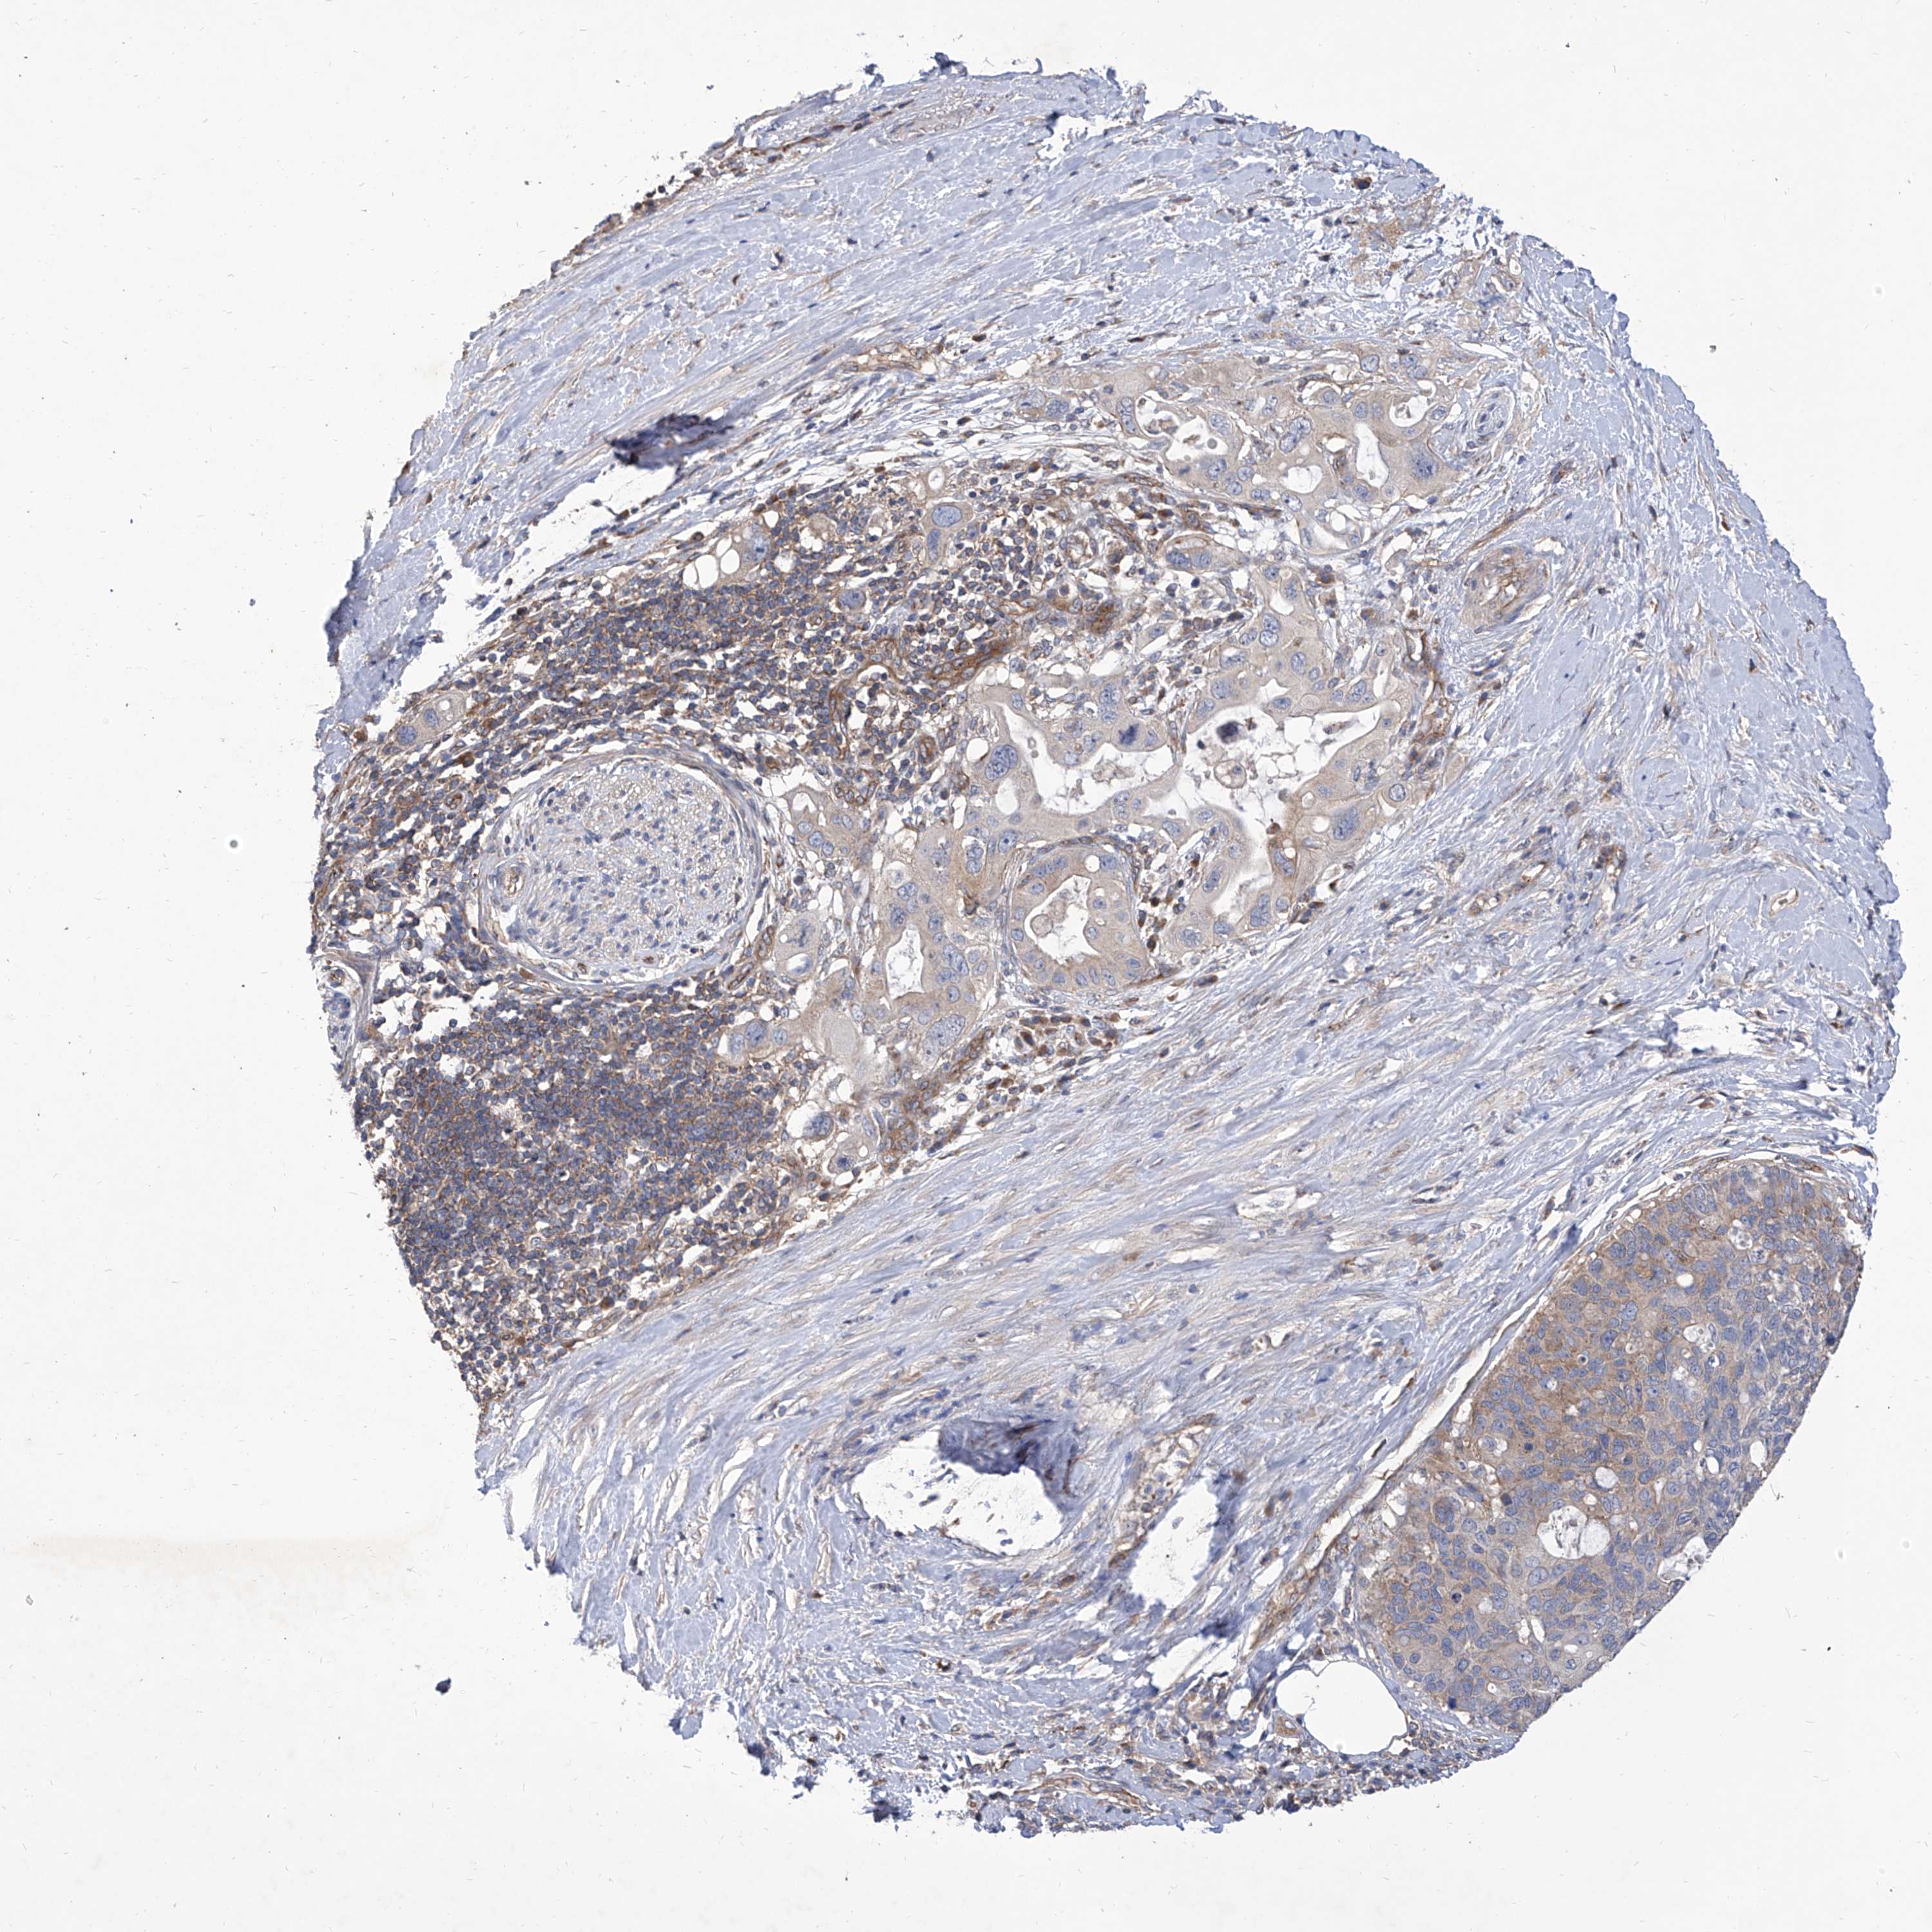

PANCREATIC CANCER - Protein expressioni

A mouse-over function shows sample information and annotation data. Click on an image to view it in a full screen mode. Samples can be filtered based on level of antibody staining by selecting one or several of the following categories: high, medium, low and not detected. The assay and annotation is described here.

Note that samples used for immunohistochemistry by the Human Protein Atlas do not correspond to samples in the TCGA dataset.

Antibody stainingi

Antibody staining in the annotated cell types in the current human tissue is reported as not detected, low, medium, or high, based on conventional immunohistochemistry profiling in selected tissues. This score is based on the combination of the staining intensity and fraction of stained cells.

Each image is clickable and will lead to virtual microscopy that enables deeper exploration of all samples and also displays staining intensity scores, fraction scores and subcellular localization as well as patient and tissue information for each sample.

Antibody HPA030164

Antibody HPA030165

Antibody HPA030166

Staining

High

Medium

Low

Not detected

Intensity

Strong

Moderate

Weak

Negative

Quantity

>75%

75%-25%

<25%

None

Location

Nuclear

Cytoplasmic/membranous

Cytoplasmic/membranous,nuclear

Adenocarcinoma, NOS